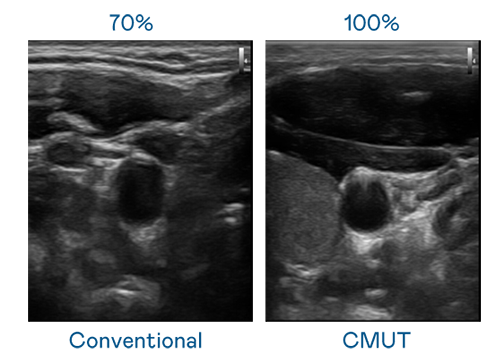

CMUT 技術是一種用電容式微機電元件來產生超音波訊號的技術。與傳統 PZT 壓電式技術相比,CMUT 頻寬增加 30%,更寬頻的超音波訊號讓影像解析度大幅提升,是實現高影像品質醫療超音波掃描、促進精準醫療發展的關鍵技術。

超音波影像的解析度高低,首先取決於探頭能發出的訊號頻寬。yy易游 CMUT 可提供高清晰的超音波訊號,提供高頻寬、高靈敏度、影像紋理細節更高的超音波影像,協助醫護人員縮短影像判讀時間及利用精準的醫療影像進行診斷。